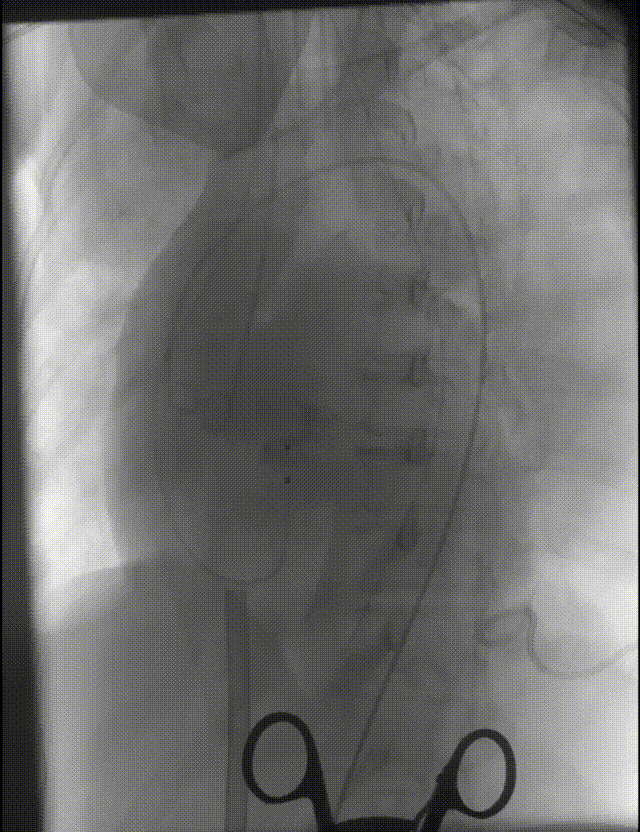

根部造影

可见大量反流 横位心 升主扩张

18mm球囊预扩,无腰有漏,冠脉显影良好